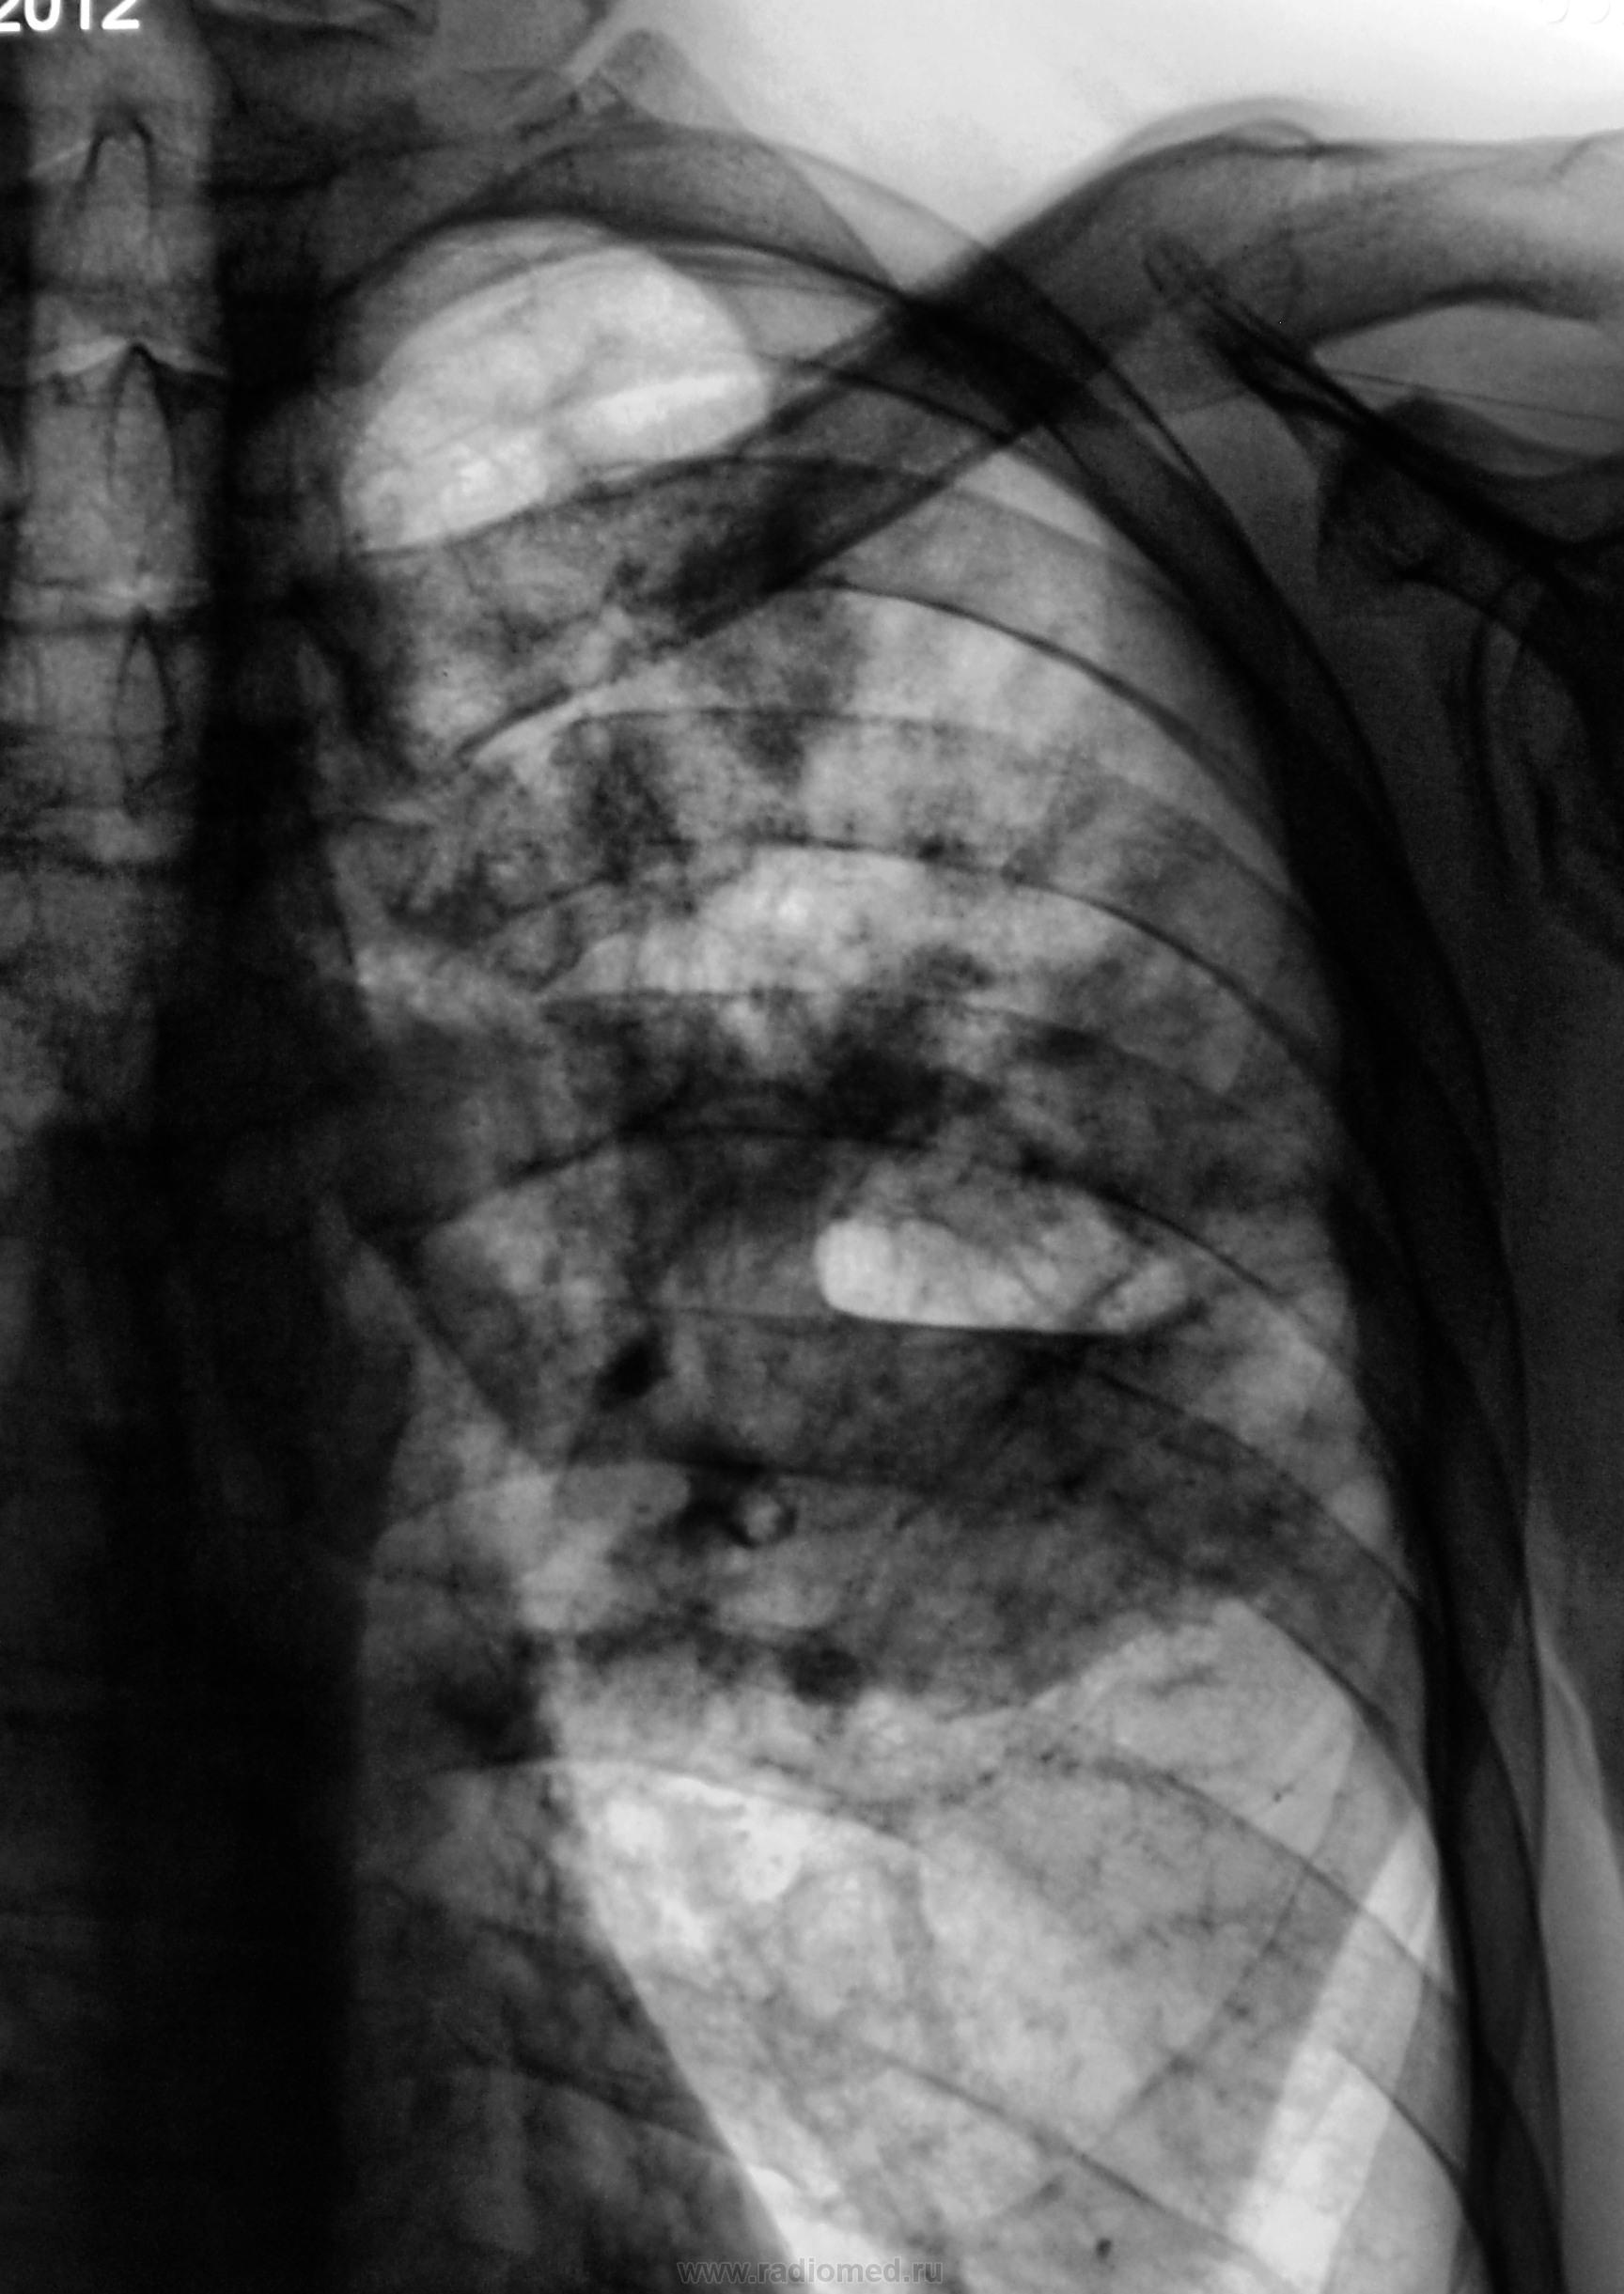

Кавернозный туберкулез с распадом?

Абсцедирующая пневмония верхней доли слева.

Такая кавернища?

деструктивная пневмония

Вначале ТБЦ. Если палочек не найдут, то пневмония.

Палочек не нашли.

Да, вроде классика - температура выше 39, мокрота с "зеленцом" валит, но пока не воняет, похужело последнюю неделю, похужело и сильно.

было бы интересно посмотреть  и уточнить локализацию процесса. Картина соответствует  инфильтративному туберкулезу с нарушением дренажной функции бронха. Поэтому МБТ пока не обнаруживаются.

Картина соответствует деструктивной пневмонии.

А бронх-то верхнедолевой слева сужен и как будто конусовидно. Очень может быть первопричина ТАМ.

До тут оказался туберкулёз.

Всем подтвержден. Пробами подтвержден, микроскопией. Оказывается еще была пункция. Информация получена от фтизиатра. Пациент в областной туббольнице.

Скиалогическая динамика сделана посредством КТ в диспансере.